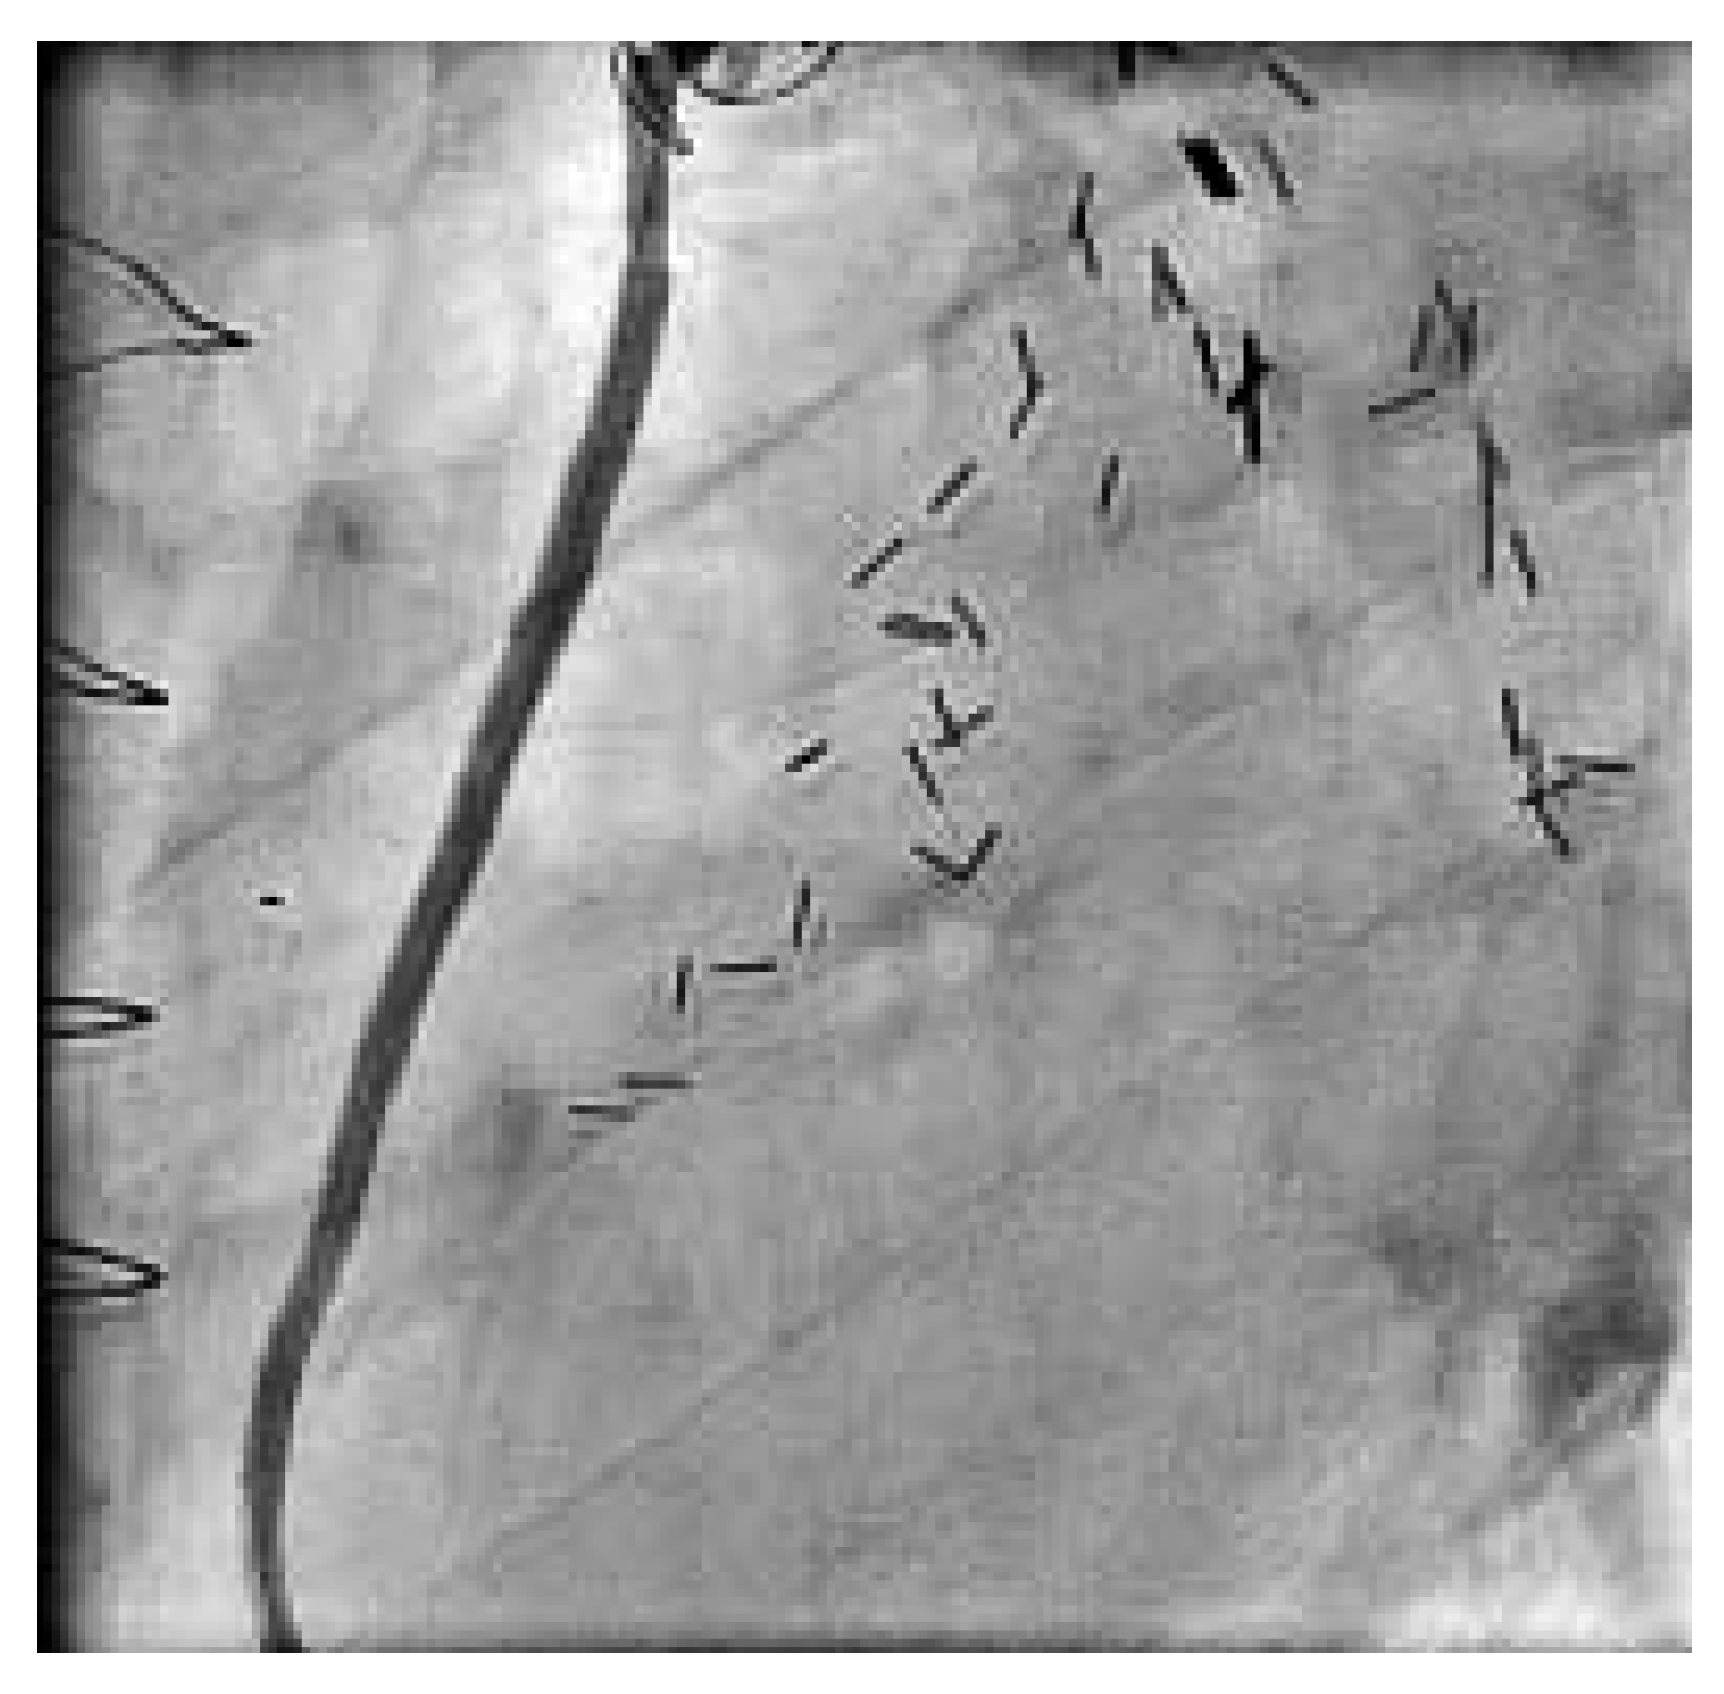

Abbildung 3. Einlage zweier langer beschichteter Stents bis über dem mittleren Gefässdrittel, wobei die Kontrastmittelsäule immer noch im proximalen Gefässanteil still steht.

Der 74jährige Patient wurde 1991 chirurgisch revaskularisiert (LIMA zu Diagonal-Ast und RIVA, Venengraft zum Ramus intermedius und Posterolateral-Ast [PLA]. 1999 wurde eine perkutane Intervention am RCAmit Stent-Einlage vorgenommen. Zwei Jahre später wurde der Venengraft mit einem Stent versorgt und der RCA rekanalisiert, erneut dilatiert und eine Brachytherapie appliziert. Im Herbst 2003 begann der Patient erneut über typische und reproduzierbare Präkordialgien, entsprechend einer CCS-Klasse III, zu berichten. Eine Rekoronarangiographie zeigte weiterhin einwandfreie Verhältnisse des LIMA- und des gestenteten Venengraftes, die RCA war jedoch am Abgang langstreckig verschlossen (Abb. 2). Der Herzchirurg war der Meinung, dass eine erneute perkutane einer chirurgischen Revaskularisation vorerst vorzuziehen wäre. Eine intravenöse Abciximab-Gabe wurde begonnen. Nach schrittweiser Drahtpassage, alternierend mit repetitiver Ballondilatation bis über die Bifurkation, intrakoronarer Nitrat-Gabe und Einlage zweier langer beschichteter Stents bis über dem mittleren Gefässdrittel, stand die Kontrastmittelsäule immer noch im proximalen Gefässanteil still (Abb. 3). Wir entschieden uns zur Verwendung des «Export»-Thrombus-Aspirationskatheters. Erst nach mehreren Durchgängen mit dem Aspirationskatheter, bei denen thrombotische Debris aspiriert wurden, kam das grosse Gefäss zur Darstellung und wurde der Fluss wieder hergestellt. Das angiographische Resultat war nach Vervollständigung der Intervention sehr zufriedenstellend (Abb. 4). Der Patient war nach der Intervention während 8 Monaten beschwerdefrei und leistungsfähig. Aufgrund eines Prostatakarzinoms wurden mehrere urologische Eingriffe und eine lokale Bestrahlungstherapie notwendig, weshalb Clopidogrel und die orale Antikoagulation sistiert werden mussten. Die perioperative Periode verlief ohne kardiale Komplikationen, der Patient jedoch wurde wieder symptomatisch (CCS-Klasse II). Nicht zuletzt, weil nun wahrscheinlich eine chirurgische Revaskularisation nicht mehr zu umgehen ist, kann sich der Patient zurzeit noch nicht zur diagnostischen Koronarangiographie entschliessen.